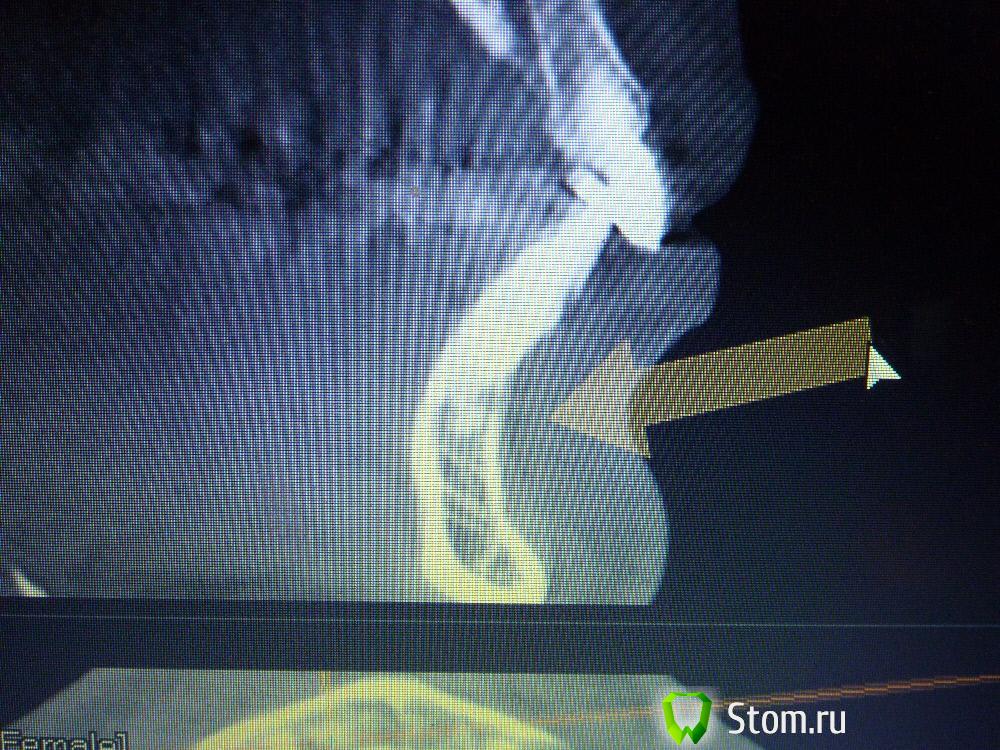

IvanK Опубликовано 25 ноября, 2011 Поделиться Опубликовано 25 ноября, 2011 Коллеги , посоветуйте Ваш план лечения.Пациентка обратилась с целью протезирования. Была направлена на ОПТГ. Обнаружены "кисты".Предположены амелобластома или первичная киста. Направлена на кафедру в 1 мед. Сказали, что "обычные кисты".Вижу 2 варианта:1). эндодонтическое лечение, цистэктомия, гистология, резекция верхушек корней, наблюдение, далее костная пластика?, имплантация. 2) Удаление зубов с периапикальными изменениями + 8-ка, гистология, пластика, имплантация боковых отделов. Ссылка на комментарий

Corvalus Опубликовано 26 ноября, 2011 Поделиться Опубликовано 26 ноября, 2011 Эндодонтическое лечение: 45,44,33-го тоже он в зоне кисты,34,36. Хуже дела обстоят с 35-м, глянуть бы прицельный снимок, если периапикальные изменения есть, то шуруп трудно достать будет. Обязательно реэндодонтия 43. Далее цистэктомия без всяких резекций с обязательной гистологией. Заполнять кисты не стал бы, достаточно крови, очаг гнойный. Через несколько недель парадонтологическое лечение, после костная пластика с отсроченной имплантацией. И в конце рациональное протезирование одиночными коронками. При нормальном эндодонтическом лечении рецедива кист не должно быть, а если и будет, то не на всех зубах сразу. Себе зубы удалять не стал бы, опыт лечения таких зубов есть, с имплантацией всегда решить можно по ходу поступления проблем. Второй вариант имеет место быть. Объяснить пациентке все за и против, пусть сама выбирает. Ссылка на комментарий